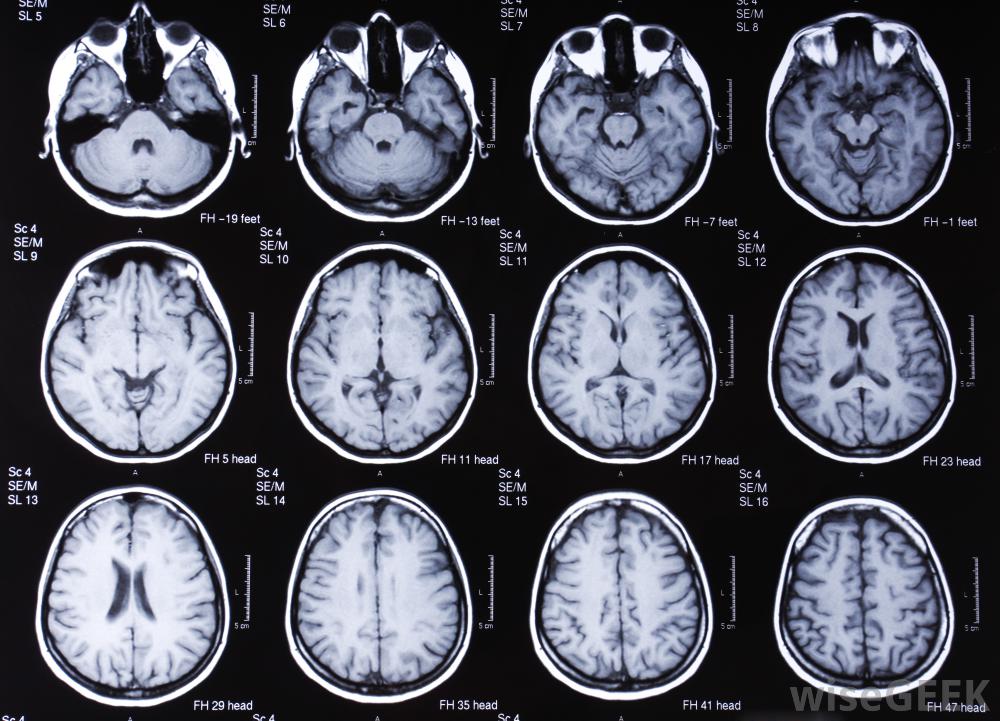

对大脑进行核磁共振扫描。